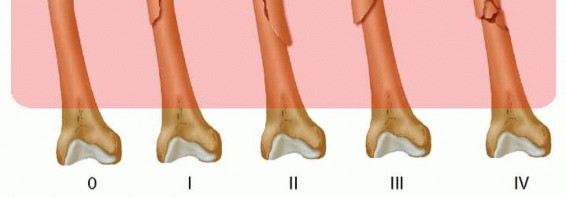

Classifications and Relative Indications It is important to assess the extent of the fracture both proximally and distally with proper radiographs. Proximally, CT scans can supplement plain radiographs to determine fracture line extension into the peritrochanteric region and to check for occult femoral neck fractures. Distally, CT imaging is helpful to assess intra-articular extension and to check for coronal plane fractures. 17 All femoral shaft fractures, as classified by the Winquist system, 33 are technically suitable for retrograde femoral nailing ( FIG 3).  ---

---  FIG 3 • Winquist femoral shaft fracture classification system.33 All fracture patterns in this system are amenable to retrograde femoral nailing.

FIG 3 • Winquist femoral shaft fracture classification system.33 All fracture patterns in this system are amenable to retrograde femoral nailing.